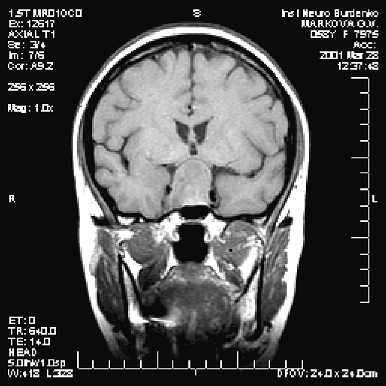

Диагностика опухоли гипофиза включает МРТ, исследование остроты и полей зрения и оценку эндокринологического статуса больного — как клиническую, так и исследование содержания гормонов (передней и задней долей гипофиза, щитовидных, половых, кортизола) в сыворотке крови. Большинство аденом характеризуется низким сигналом на Т1— и высоким — на Т2-взвешенных изображениях (рис. 2–4). Микроаденомы лучше визуализируются после внутривенного введения препарата гадолиния. КТ может иметь значение для уточнения характера костных изменений и размеров турецкого седла.

Рисунок 2. Аденома гипофиза средних размеров (МРТ, Т1-взвешенное изображение, фронтальная проекция)